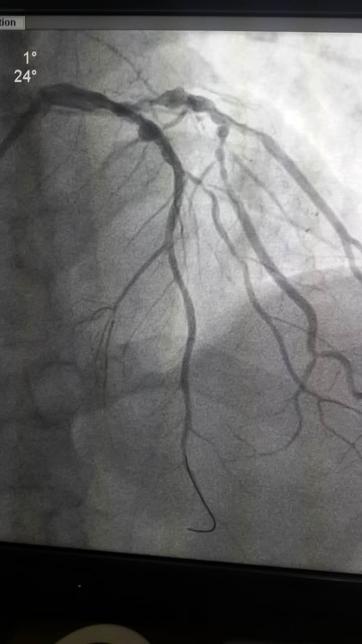

无影灯亮起,医生们站上手术台,一场没有硝烟的战争就此打响。我院心血管内一科介入医生立即展开手术。术前患者情况急转直下,血压降至60/40mmHg,心率降至40次/分,心电监护示频发室性早搏,迅速完成冠状动脉造影检查,发现左冠前降支近段近开口处完全闭塞伴有血管瘤及瘤样扩张,左回旋支多发瘤样扩张、管腔最重处达85%狭窄,手术风险极大,与陪同人员及与家属电话多次沟通后,在前降支球囊扩张后植入药物支架一枚,血管再通,前向血流恢复3级。在胸痛中心医护人员的努力下,为患者最快速度开通了“罪犯”血管,使患者转危为安,安返病室。手术仅45分钟(含与家属沟通时间),而D-to-B(进医院大门至首次球囊扩张)时间由之前台均约240分钟缩短至93分钟,执行先救治、后收费使得疾病及时救治,没有延误。我院胸痛中心再传捷报,绿色通道为拯救生命争得了时间。

手术前 手术后